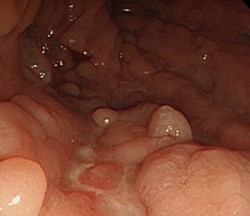

Αφαιρεθέντες πολύποδες, ενδοσκοπικά και χειρουργικά (Ευγενική παραχώρηση Dr. V. Penopoulos)

Καλόηθης πολύποδας — κορυφαίο σημείο εντύλιξης (Ευγενική παραχώρηση Dr. V. Penopoulos)